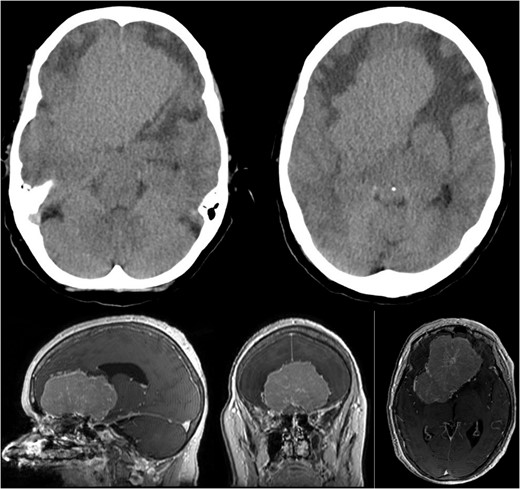

Brain CT imaging unveiled a hypodense fronto-basal lesion measuring 9–10 cm with finger-shaped perifocal edema (Fig. 1). contrast-enhanced cMRI provided more precise dimensions of the lesion (52 x 41 x 82 mm), demonstrating mild compression on both lateral ventricles and posterior displacement of the right middle cerebral artery and both anterior cerebral arteries without signs of hydrocephalus or perfusion disturbances (Fig. 1) and the bilateral COF anastomoses (Fig. 2) .

Showing the CT imaging with a hypodense fronto-basal lesion with finger-shaped perifocal edema and the T1-weighted MRI image with homogenous contrast-enhancing frontobasal lesion demonstrating mild compression on both lateral ventricles and posterior displacement of the right middle cerebral artery (MCA) without evidence of hydrocephalus.